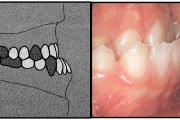

) Röntgenülesvõte. Ülemise esimese jäävmolaari lõikumine on takistatud 2. piimamolaari tõttu

Esimese jäävmolaari ektoopiline lõikumine